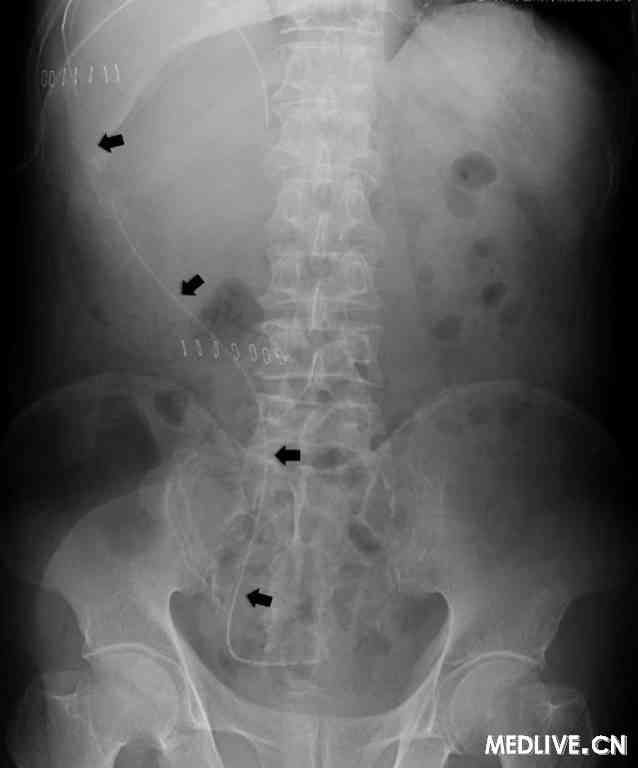

在此情况下,我们决定在建立心包窗后2个月时采用丹佛分流管行胸膜腹膜分流(见图2)。从第5肋间向右侧胸膜腔插入1根有孔的细胸膜导管(16 Fr),并通过1个皮下通道将其连接到主泵上,后者有2个单向阀并被固定在右侧肋部边缘皮下。穿过右上腹直肌向腹腔插入1根腹膜导管(见图3)。结果,该患者的乳糜胸明显好转,相应症状消失(见图4)。患者在17个月后死亡,在死亡前不再需要对乳糜胸采取进一步治疗,胸膜腹膜分流也未出现任何问题。

图3  丹佛胸膜腹膜分流管(箭头)被置入腹腔